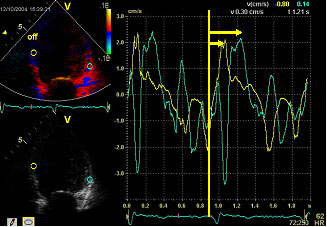

Figure 4

Septum to lateral wall delay measured as the time difference between the time interval from the QRS beginning to the peak of the systolic contraction of the basal septal and lateral segments in the 4 chambers apical view as Bax et al described. A maximum delay to peak systolic tissue velocity > 60 ms is considered as a criterion of LV intraventricular asynchrony.

Among the different echo-measurements, the easiest one to obtain is the septum to posterior wall delay, described by Pitzalis et al using the M-mode (Figure 3). Later, more sophisticated determinations applying Doppler Tissue Imaging derived parameters as described by the group of Bax (Figure 4) and the studies of Yu et al, also demonstrated their usefulness in determining LV intraventricular asynchrony. More recently, some parameters derived from Speckle Tracking Imaging and three-dimensional echo have also shown their usefulness in determining the presence of intraventricular asynchrony, although the degree of complexity in obtaining and interpreting these images increases.